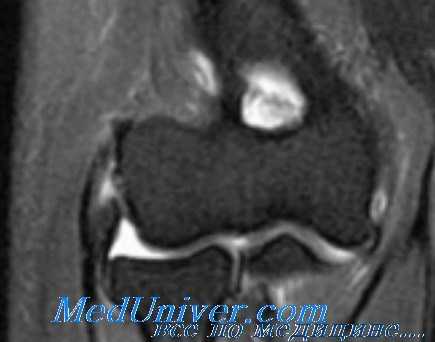

Диагноз медиальный эпикондилит устанавливается на основании клинических признаков и характерного анамнеза. Для исключения костно-суставной патологии проводится рентгенография локтевого сустава в двух проекциях. Дифференциальная диагностика осуществляется с повреждением связок (разрывом или растяжением локтевой коллатеральной связки), медиальной нестабильностью локтевого сустава, шейной радикулопатией и синдромом кубитального канала. Для оценки состояния сухожильно-связочного аппарата назначается МРТ локтевого сустава, для уточнения состояния мышц – электромиография, для исключения нарушений со стороны нервной системы – консультация невролога и детальное неврологическое исследование.